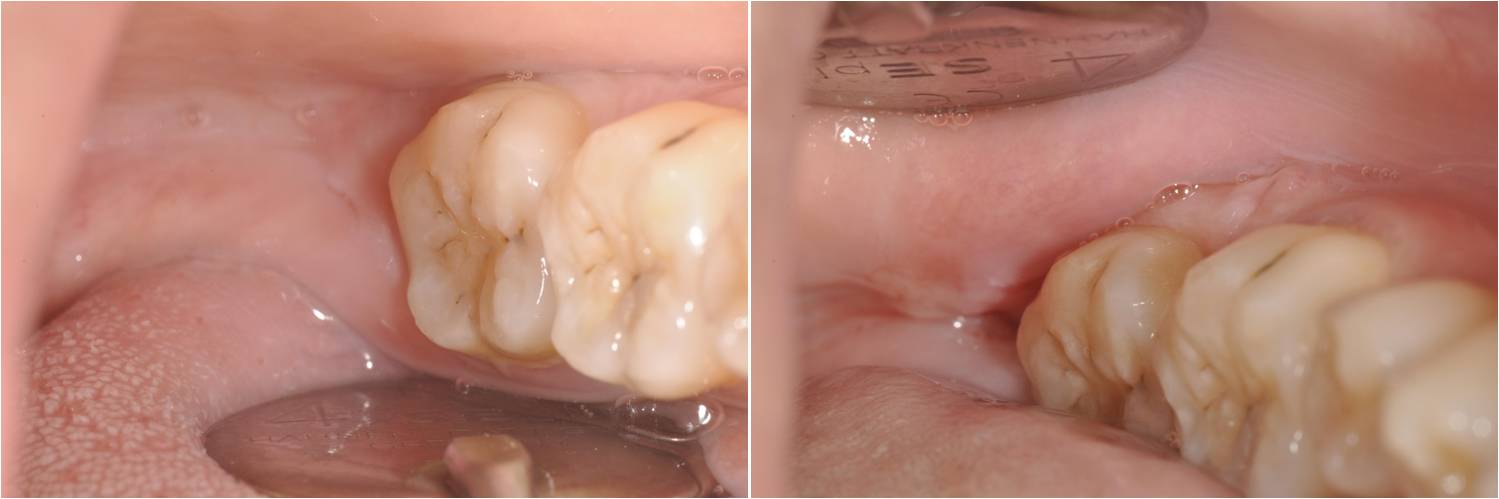

拔牙後傷口處理-阻生齒萌發異常-#38

口腔外科

拔牙後傷口處理